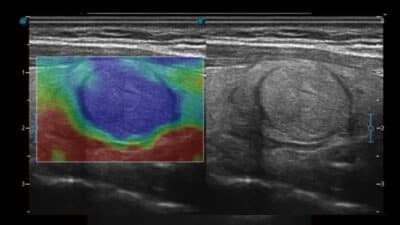

Zobrazování C-xlasto

- Umožňuje komplexní kvantitativní analýzu pružnosti.

- Systém rychle vypočítá poměr deformace a zobrazí neobvykle tvrdé/měkké anomálie v tkáni.

- Více sond zajišťuje dobrou reprodukovatelnost a konzistentní

kvantitativní elastické výsledky.